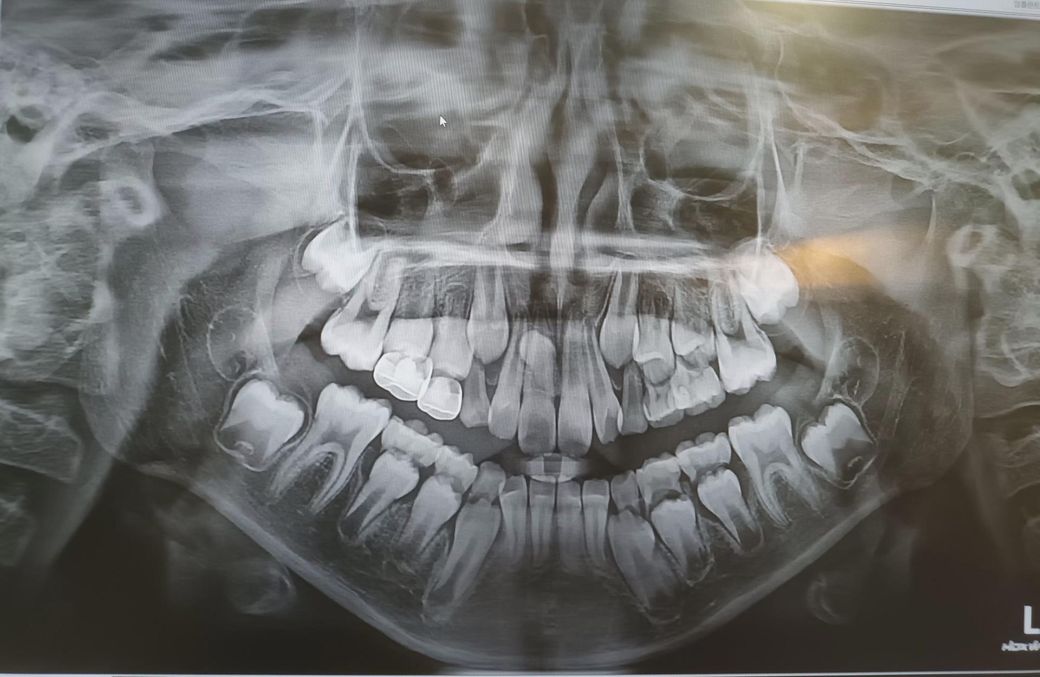

10살 남아 과잉치가 있는데 동네병원에서 수술해도 될까요?

과잉치가 있다는 걸 알게 되었습니다

윗쪽 앞니에 있다고 하더라구요

과잉치 발치는 일단 동네 병원에 가셔서 발치가 가능한지 상담을 받아보시고 가능하면 발치를 하면되지만 저정도 케이스라면 대학병원으로 가셔야될것같습니다.

2차원 사진으로는 판단이 어렵고 ct를 찍어서 얼마나 깊이 있는지, 앞 영구전치가 얼마나 가까운지에 따라 난이도가 다릅니다. 다만, 동네 어린이 치과에서도 매복 과잉치 발치 수술 경험은 많을 겁니다. 거기서 할 수 있다고 하면 믿고 치료 받으시면 됩니다.